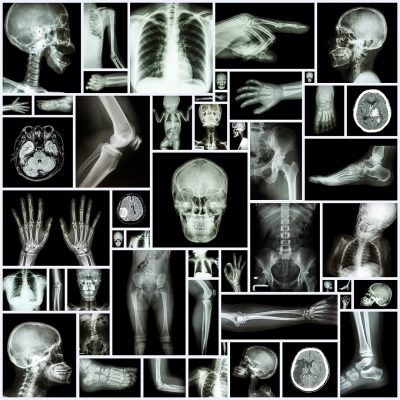

Este é um recurso que está disponível oferecido em formato JPG. Este é um dos formatos de imagem mais utilizados no mundo, conhecido por sua alta compatibilidade e qualidade visual, ideal para projetos digitais e impressos. O arquivo possui tamanho de 3.13 MB e está disponível sob a licença Grátis. Esta licença permite o uso do recurso tanto em projetos pessoais quanto comerciais.